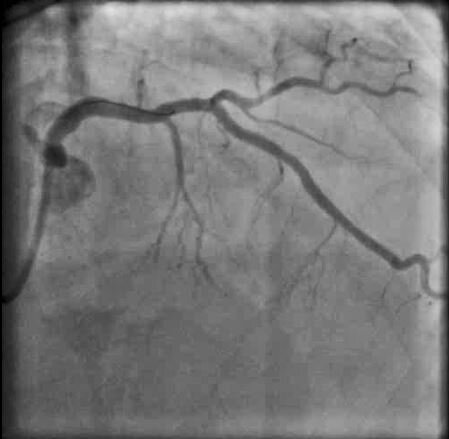

Angiogram shows severe LAD stenosis with thrombosed plaque

Post-stenting: Absolutely gorgeous result!